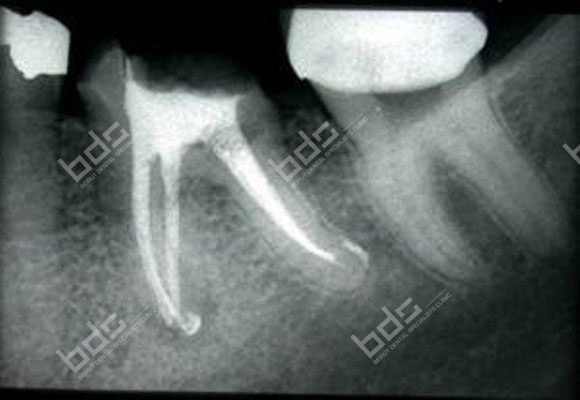

Root Canal Therapy

Endodontic treatment is necessary when the pulp, the soft tissue inside the root canal, becomes inflamed or infected. The inflammation or infection can have a variety of causes: deep decay, repeated dental procedures on the tooth, or a crack or chip in the tooth. In addition, an injury to a tooth may cause pulp damage even if the tooth has no visible chips or cracks. If pulp inflammation or infection is left untreated, it can cause pain or lead to an abscess.

Many endodontic procedures are performed to relieve the pain of toothaches caused by pulp inflammation or infection. With modern techniques and anesthetics, most patients report that they are comfortable during the procedure

Our endodontists use their special training and experience in treating difficult cases, such as teeth with narrow or blocked canals, or unusual anatomy. They also use advanced technology, such as operating microscopes, ultrasonics and digital imaging, to perform these special services.

Endodontic retreatment with broken file

Endodontic retreatment with multiple apices

Endotontic retreatment with peri apical reaction

Case 1: Before (broken files)

Case 1: Completion of root canal therapy

Case 2: Before

Case 2: After